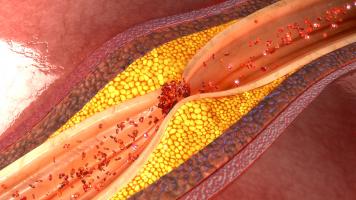

ATHÉROSCLÉROSE : Des nanoplastiques à côté de la plaque

ATHÉROSCLÉROSE : Et si le cholestérol n'était pas le seul lipide impliqué ?

ATHÉROSCLÉROSE : Réaliser les promesses des sphingolipides

ATHÉROSCLÉROSE : La plaque plus tardive mais plus nocive chez les femmes ménopausées

Actualité publiée le 16/06/2023ATHÉROSCLÉROSE : Prévenir l'obstruction des artères en boostant l’autophagie

ATHÉROSCLÉROSE : Le nutraceutique qui dissout les blocages athéroclérotiques

ATHÉROSCLÉROSE : Mais comment stabiliser la plaque ?

Actualité publiée le 19/07/2022ATHÉROSCLÉROSE : Le laser qui vaporise la plaque